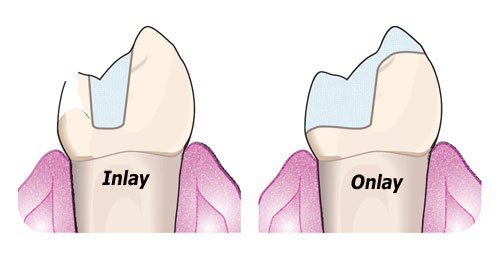

در مواقعی که قسمت از دست رفته دندان های خلفی وسیع باشد و امکان انجام ترمیم های مستقیم نباشد و تراش برای روکش باعث از دست رفتن بقیه نسج باقی مانده شود، استفاده از آنله و اینله (بخصوص سرامیکی) خیلی سودمند می باشد.

اینله

پروتزی که قسمتی از سطح اکلوزال و حداقل یکی از سطوح پروگزیمال را بازسازی می کند و جنس ان می تواند تمام سرامیک، کامپوزیت لابراتواری، طلا یا آلیاژ باشد.

آنله

پروتزی که تمام سطح اکلوزال و حداقل یکی از سطوح پروگزیمال را بازسازی می نماید و جنس آن می تواند تمام سرامیک، کامپوزیت لابراتواری، طلا یا آلیاژ باشد. آنله حتما باید حداقل یکی از کاسپ ها را پوشانده و بازسازی کند.